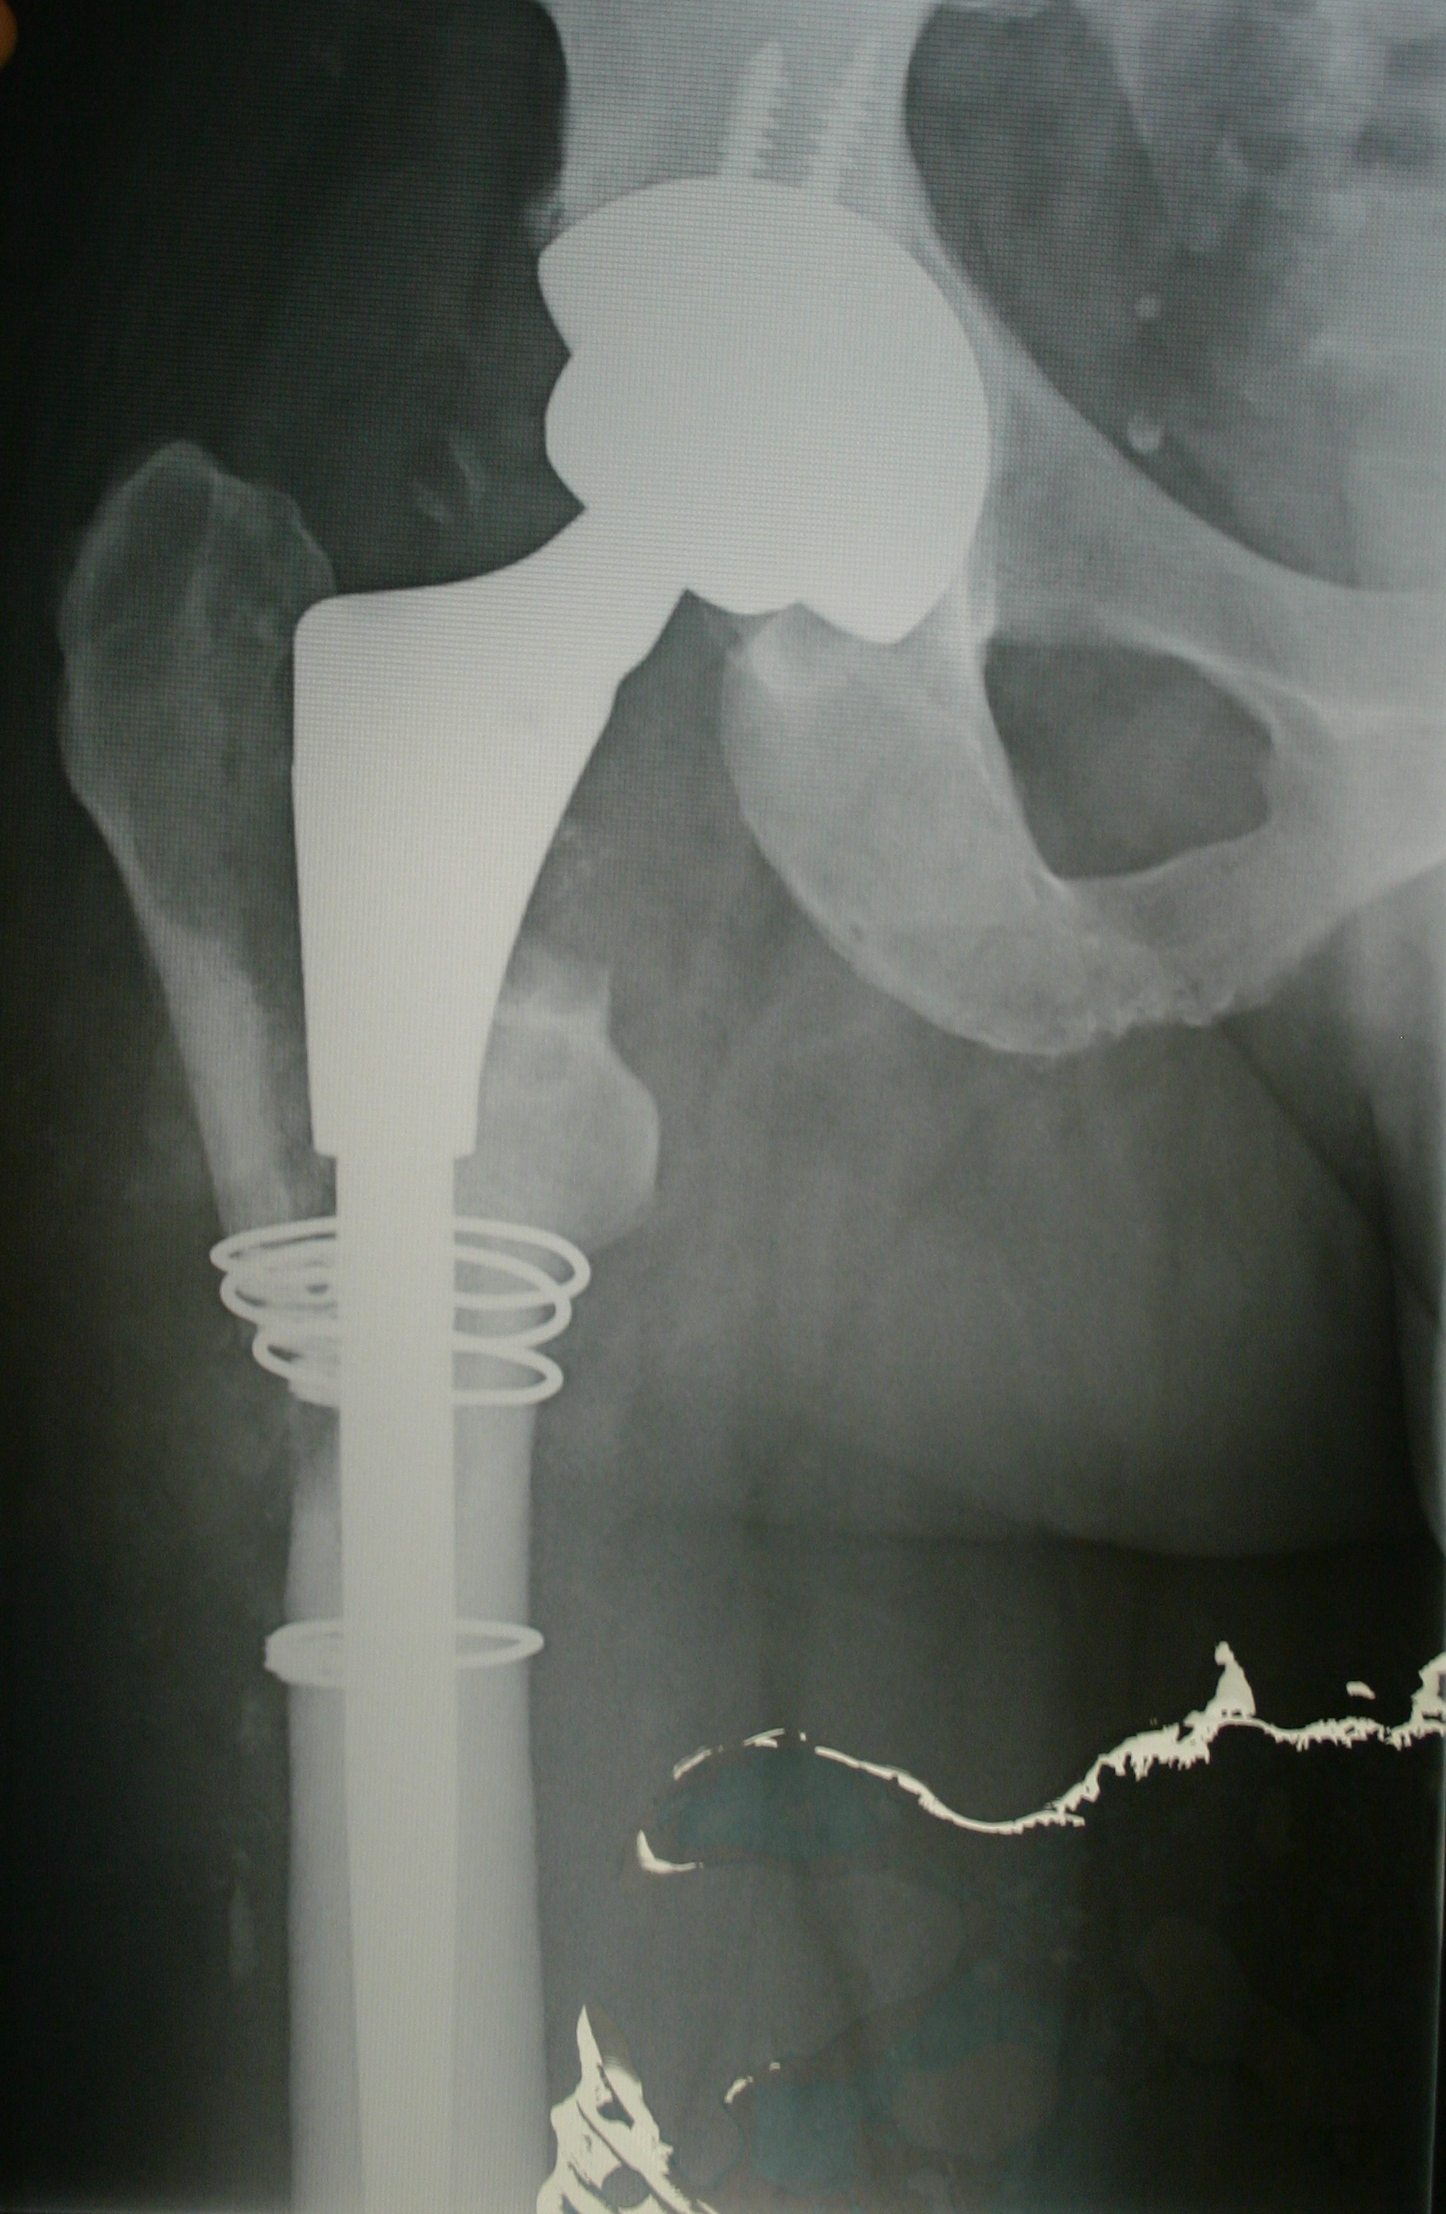

Visited the surgeon and he was very happy with the progress – Day 26 post Operation. Total hip Revision – from S&N Birmingham Spectron Metal on Metal to Zimmer Revision Ceramic on Ceramic Hip.

Considering that I had the femur split, two bone grafts and new hip implants (both press fit), the healing of the bone, tissue and wound is great and in terms of mobility of the new joint all is great!

Below are two of the X-Rays taken on the 26th Sept 2011. The marks on the X-Rays are courtesy of the younger person in the house who spilled their drink…